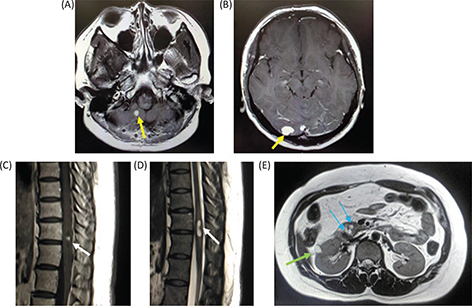

At the age of 26, the patient underwent surgical treatment for cerebellar hemangioblastoma. She also had a spinal cord hemangioblastoma at 11th thoracic vertebra level, a renal cyst and multiple pancreatic cysts (Figure 2).

Figure 2. Magnetic resonance imaging of the patient. (A and B) Gadolinium (Gd)-enhanced T1-weighted image of cerebellum when the patient was 26 years old. The patient had multiple cerebellar hemangioblastomas. (C) Gd-enhanced T1-weighted image of the lower thoracic cord. A small hemangioblatoma with a syrinx is shown. (D) T2-weighted image of the lower thoracic cord. (E) T1-weighted image of the abdomen. A renal cyst and multiple pancreatic cysts are shown.

Magnetic resonance imaging (MRI) of the head showed a Gd-enhanced well-circumscribed mass on the left retrobulbar optic nerve in the orbital, and three-dimensional MRI showed the tumor enveloped the left optic nerve (Figure 4).